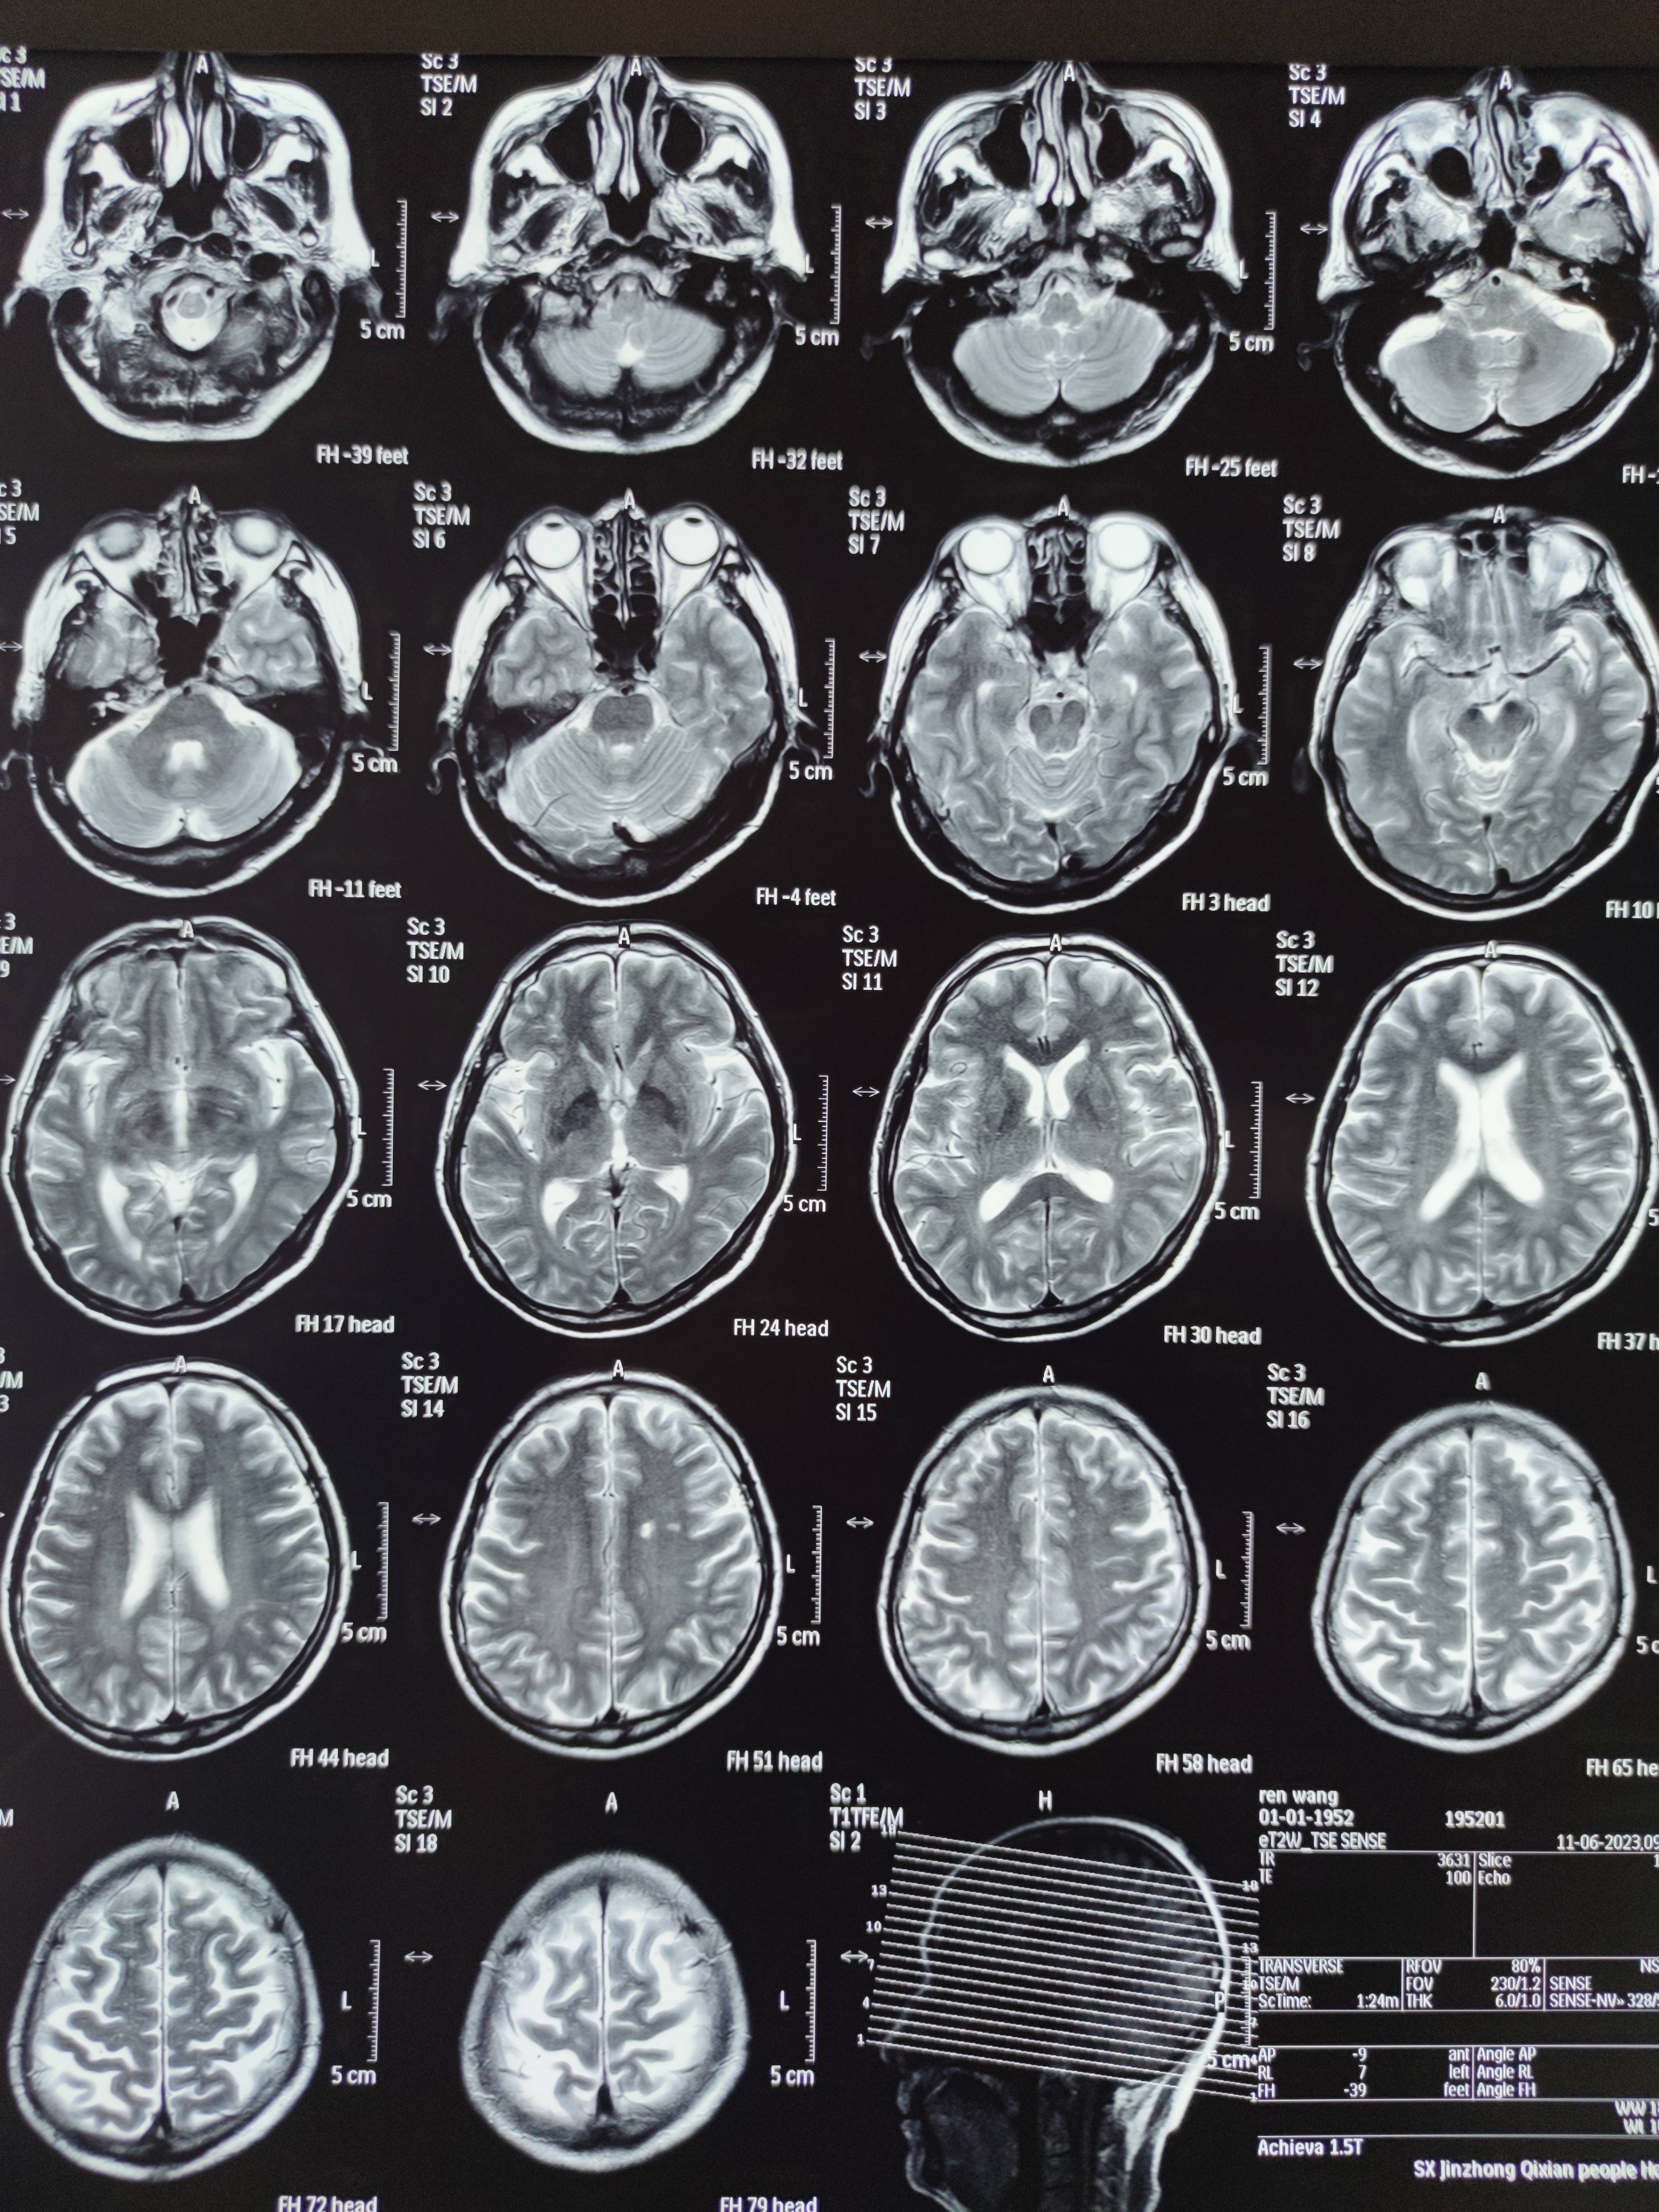

四月份癌胚抗原还是5.6,这个月到8了,持续升高。做了核磁增强,左侧桥小脑角哪有个地方不确定。肝脏核磁平扫弥散有两个点状高信号,转移也排不了,胃肠镜正常,左颈部有个变圆的淋巴结,保险点是不该加个化疗药了?咨询了陈波主任,等结果的吧!图片